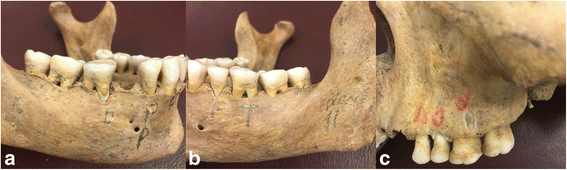

Methods: The study material comprised 12 dry skulls with maxilla and mandible. Artificial defects (dehiscence, tunnel, and fenestration) were created on anterior, premolar and molar teeth separately using burs. In total 14 dehiscences, 13 fenestrations, eight tunnel and 16 without periodontal defect were used in the study. These were randomly created on dry skulls. Each teeth with and without defects were images at various vertical angles using each of the following modalities: a Planmeca Promax Cone Beam CT and a Digora photostimulable phosphor plates. Specificity and sensitivity for assessing periodontal defects by each radiographic technique were calculated. Chi-square statistics were used to evaluate differences between modalities. Kappa statistics assessed the agreement between observers. Results were considered significant at P < 0.05.